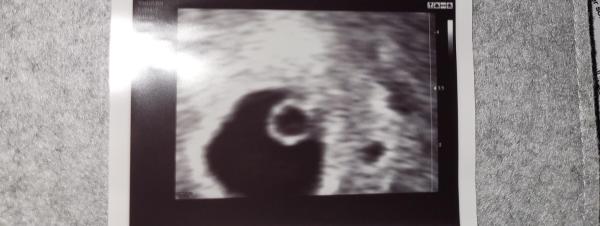

Hallo ihr lieben, Gestern wurde der erste Ultraschall gemacht. Viel erkennt man ja noch nicht. Leider habe ich die Ramzi Methode nicht so ganz verstanden, bzw man liest überall etwas anderes. Wer könnte mal eine Vermutung abgeben, ob das Pünktchen ein Mädchen oder ein Junge werden könnte? Vorab : Beides ist herzlich willkommen und mir ist klar, dass es nicht sicher ist. Vielen Dank und liebe Grüße.

Das Bild wurde mit einem vaginalen Ultraschall in der 6. SSW gemacht:)